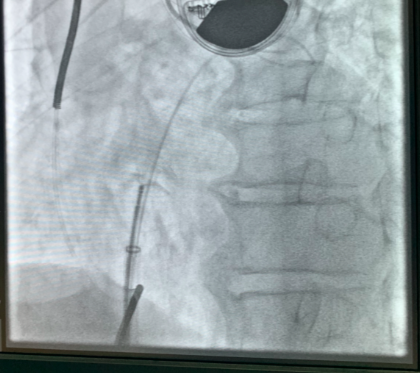

经过术前筛选排查及专家审核,认为患者存在心房分流术指征,局麻下行心房分流器植入。右心导管测量结果:肺动脉压50/34(39)mmHg,左心房压30/16(20)mmHg,右房压10/8(8)mmHg。经卵圆窝房间隔穿刺成功后送入预塑形导丝,选择6mm外周动脉高压球囊进行扩张,植入20-6心房分流器,透视及超声下观察分流器形态位置良好,测量分流器孔径约5mm,左向右分流流速1.7m/s,压差10mmHg。术后右心导管结果:肺动脉压48/32(37)mmHg,左心房压25/15(18)mmHg,右心房压6/4(5)mmHg,Qp/Qs=1.31,患者自觉症状减轻,转回普通病房。

图2:术后心房分流器形态